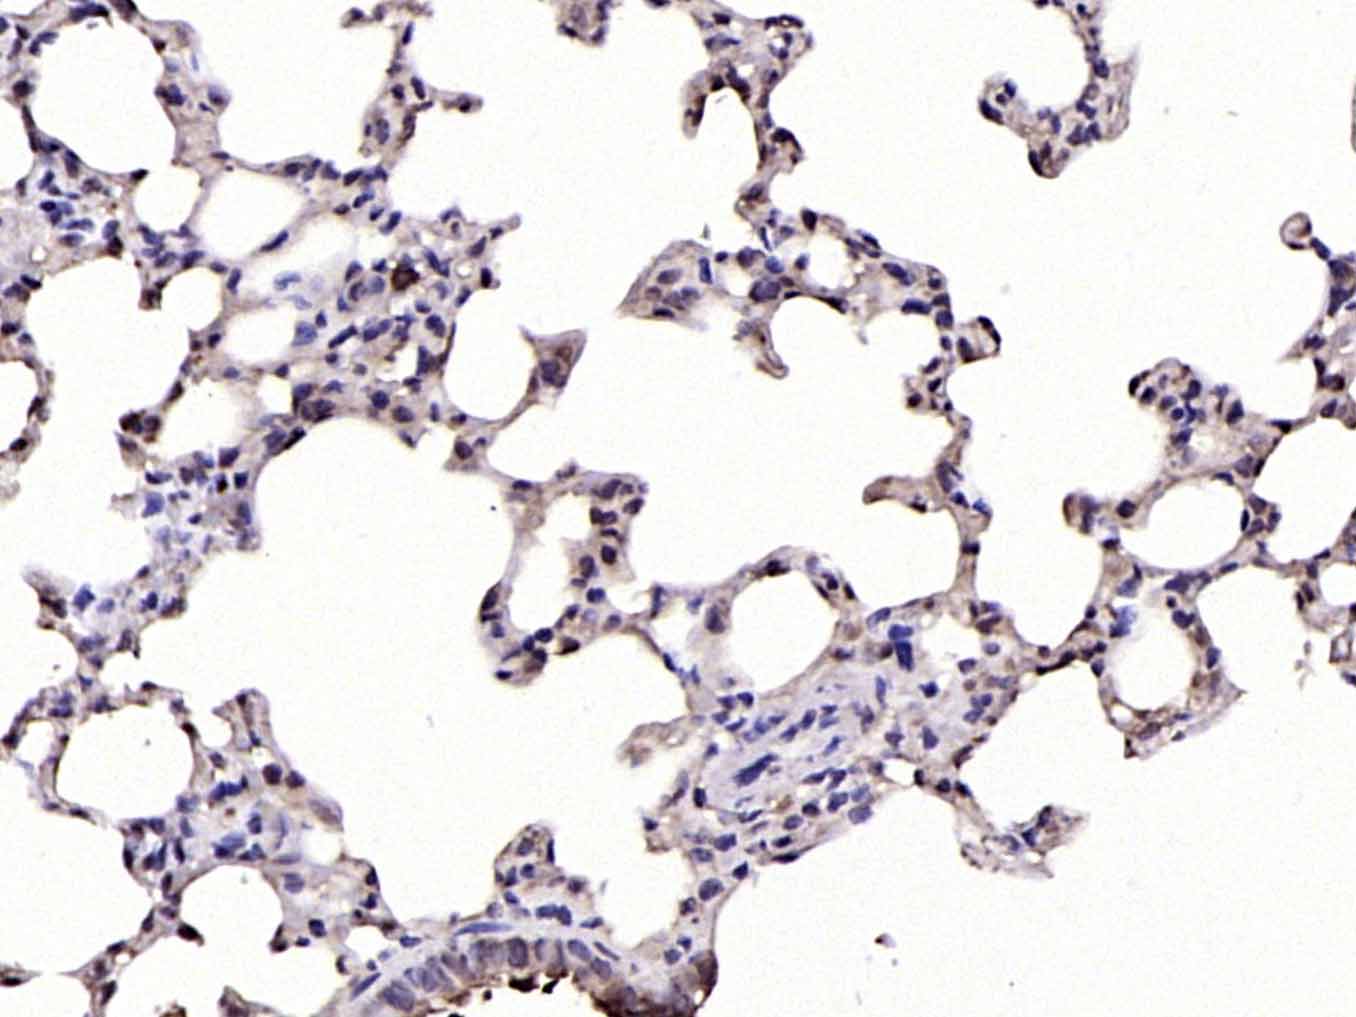

Paraformaldehyde-fixed, paraffin embedded (rat lung); Antigen retrieval by boiling in sodium citrate buffer (pH6.0) for 15min; Block endogenous peroxidase by 3% hydrogen peroxide for 20 minutes; Blocking buffer (normal goat serum) at 37°C for 30min; Antibody incubation with (phospho-IKB alpha (Ser32)) Polyclonal Antibody, Unconjugated (bs-18128R) at 1:200 overnight at 4°C, followed by operating according to SP Kit(Rabbit) (sp-0023) instructionsand DAB staining.